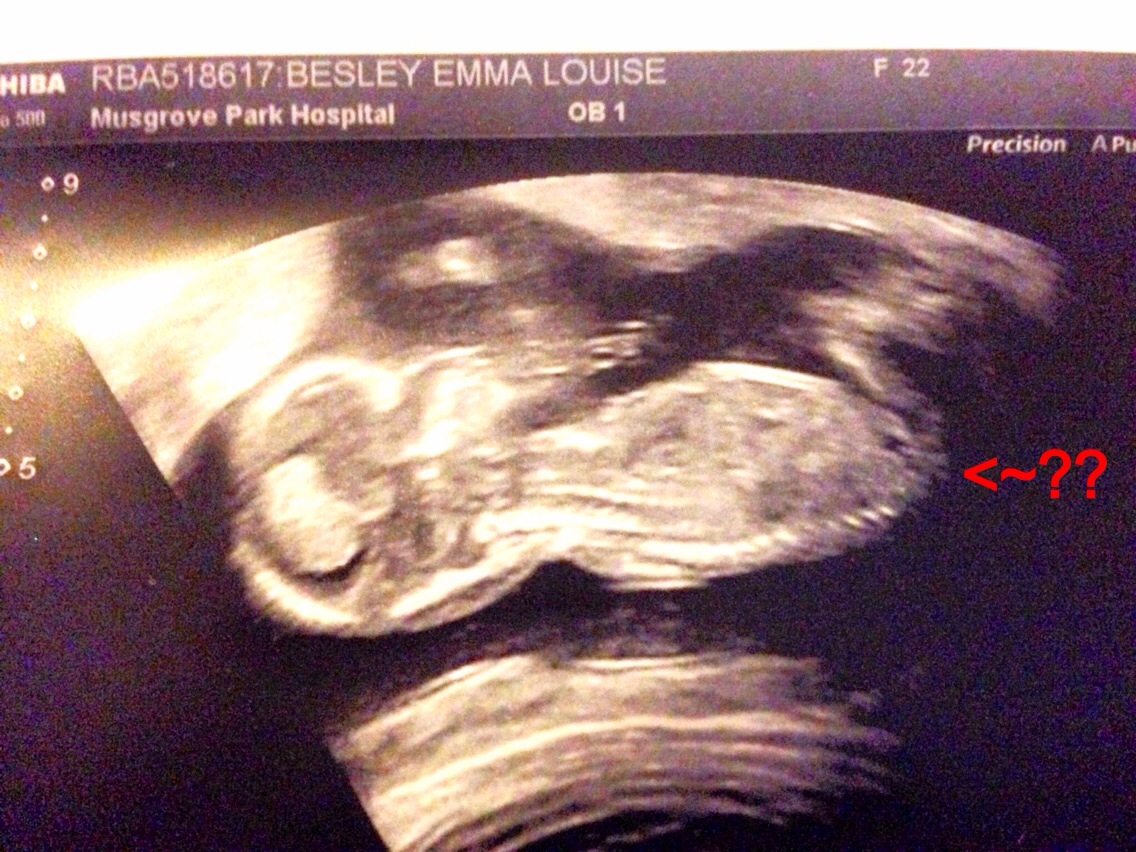

Told girl? Should I be convinced. Tech said swollen labia and clitoris.

Embryo Development external genital sex organs - angle of the dangle boy or girl ultrasound gender scan - Baby2see on this website my wife was researching the clitoris and labia appear just like in the sonogram. Does anyone know if this website is creditable?

My wife posted in another thread but this is the other pic from the same sonogram.

Second picture looks like a girl.

So with both picture would you be convince or was it was to early, she was a little over 16 weeks.

The second pic is girly. Not sure about the first pic. Looks like a lot of swelling for that stage. But I presume if the tech was knowledgeable, she would know far better what she was seeing. I'd confirm either way at your next sonogram.

At 16 weeks is not too early to get an accurate determination. All of mine have been determined by 16 weeks. But angles/skill can play a big role. The tech needs to be knowledgable and the baby needs to cooperate. But that is also true at 20 weeks, 25 weeks, 30 weeks, etc...